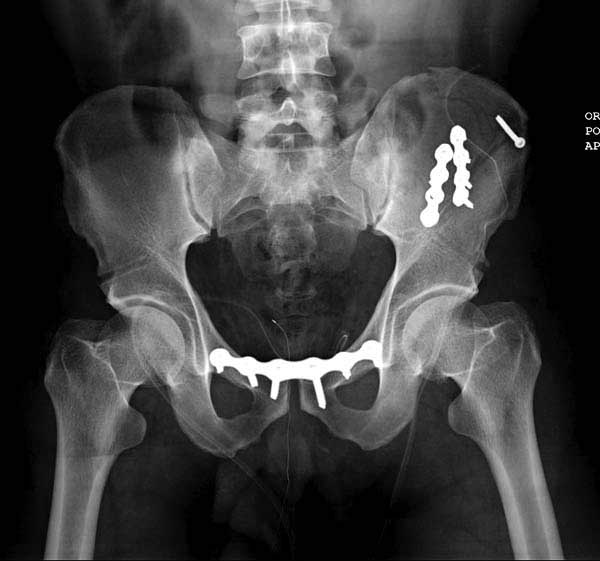

Реконструктивные пластины слабые, и для усиления необходимо установить дополнительную верхнюю пластину или оставить передний наружный фиксатор. Предпочтительным для фиксации считаю специальную для симфиза жесткую пластину из набора Joel Matta (Stryker), которая лучше, чем остальные, создает жесткость.

Здесь представлен случай 38 летнего больного (падение с высоты 9 метров) с нарушением тазового кольца. При поступлении для стабилизации передне-нижний аппарат наружной фиксации и на 6й день, вчера, операция из двух доступов.

Представлены снимки техники проведения стержней. Через место прикрепления прямой мышцы в Inferior Iliac Spine в направления вырезки создается жесткость. Weber clamp изнутри таза для репозиции, и фиксация после репозиции перелома крыла подвздошной кости. Наружный аппарат удален, нагрузка предполагается через два месяца.